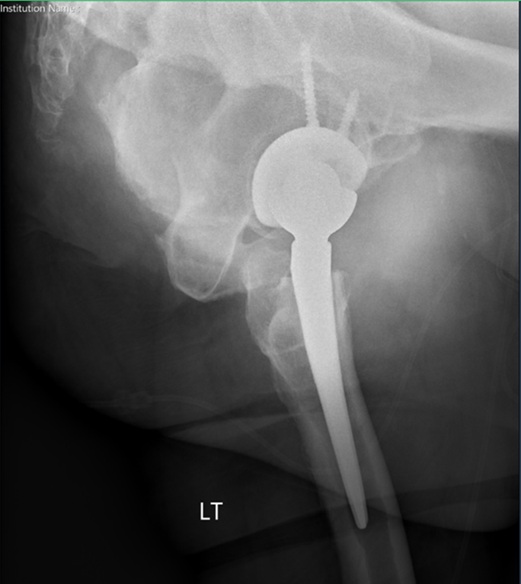

Figure 8, 9 and 10. AP pelvis, AP of the left hip, and lateral of the left hip demonstrating left reverse total hip arthroplasty without acute complication.

Post-op Radiographs

Figure 8.

Figure 9.

Figure 10.